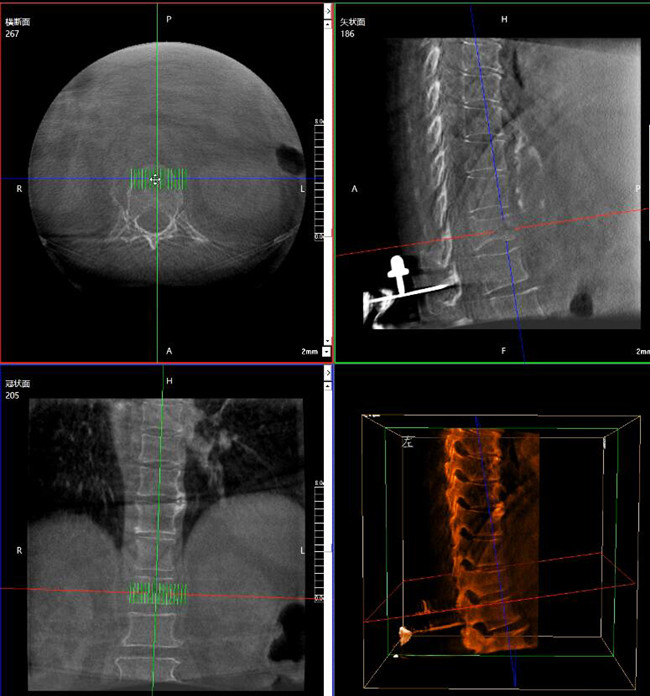

使用普爱医疗三维C形臂对患者进行胸椎影像扫描及三维重建,图像被同步传输到普爱医疗骨科机器人导航系统。

借助骨科机器人的规划软件进行术前手术路径模拟规划,找到穿刺位置和角度,操作机械臂快速完成手术入点的准确定位。

*术前规划